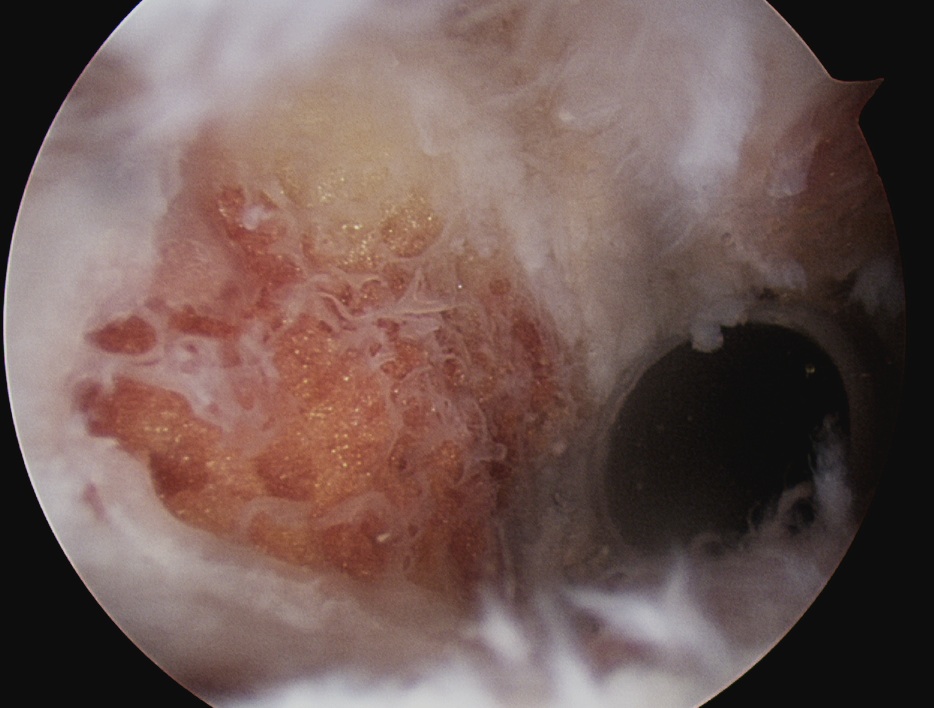

Acromioclavicular joint osteolysis

Bone Scan